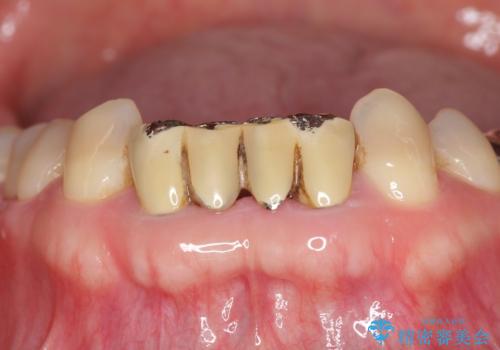

- 前歯の被せもののやり直しを希望して来院。

隣の歯もつぎはぎでプラスチックが劣化していたため、虫歯を取りセラミックでかぶせました。

保険治療の前歯の被せものの縁(マージン)が歯茎の中まで及んでいたため、歯周外科手術を行い、マージンが歯肉縁下深くならないように設定しました。